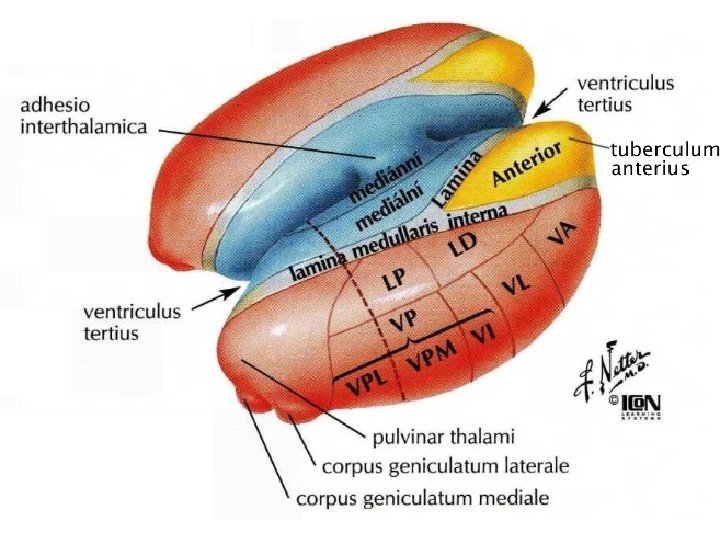

Thalamus (thalamus dorsalis) • • • „sekretářka mozku“ vše kromě čichu pulvinar (dorzálně) tuberculum anterius (ventrálně) lamina medullaris medialis + lateralis thalami adhesio interthalamica (80 %) – bez významu jádra se rozdělují se podle polohy nebo zapojení – nuclei anteriores, dorsales, intralaminares, mediani, mediales, posteriores, ventrales, reticularis – specifická senzorická jádra – specifická nesenzorická jádra – nespecifická jádra – asociační jádra

Třídění thalamických jader dle polohy nuclei anteriores, dorsales, intralaminares, mediani, mediales, posteriores, ventrales, reticularis

Specifická jádra • tractus mamillothalamicus ncl. anterior gyrus cinguli – opakované kroužení zesiluje emoce • globus pallidus ncl. VA prefrontální kůra • globus pallidus ncl. VL doplňková motorická kůra • nucleus dentatus cerebelli ncl. VL motorická kůra • lemniscus medialis et spinalis ncl. VPL senzitivní kůra • lemniscus trigeminalis ncl. VPM senzitivní kůra

Asociační jádra • ncl. LD (lat. dors. ) area cingularis posterior • čichový a limbický mozek ncl. MD (mediodors. ) prefrontální kůra (myšlení, úsudek, nálada, stav mysli – integrace se smyslovými podněty) • colliculus superior ncl. LP (lat. post. ) + pulvinar zraková a parietální asociační kůra (přitahuje pozornost k objektům v periferii zrakového pole) • ncll. P (pulvinar) frontální, temporální, parietální a okcipitální asociační kůra (integrace zrakových, sluchových, hmatových a polohových podnětů)